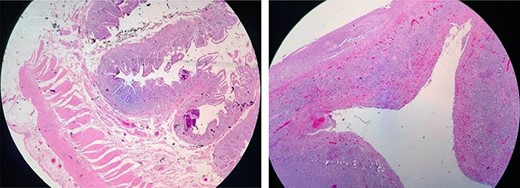

The surgical histopathology report was negative for malignancy and showed reactive changes with decreased villi crypts; a severe mixed inf lammatory infiltrate of the lamina propria was predominantly lymphoplasmacytic with accumulation o eosinophils and histiocytes,whichwere indicative of acute ulcerative ileitis with perforation. No microorganisms were identified (Fig. 2). Intestinal traffic was restored at 10 weeks. A side-to-side jejunocecal anastomosis was performed. The patient showed good evolution with a gluten-free diet and an improved clinical outcome. The patient was discharged from the surgical ward and scheduled for follow-up at the Department of Gastroenterology.

(A) Fibrinopurulent exudate and terminal ileal perforation at 20 cm from the ileocecal valve, measuring 0.3 cm in diameter. Pre-perforated areas are located at 40 and 60 cm from the ileocecal valve. (B) Resection of the ileum.